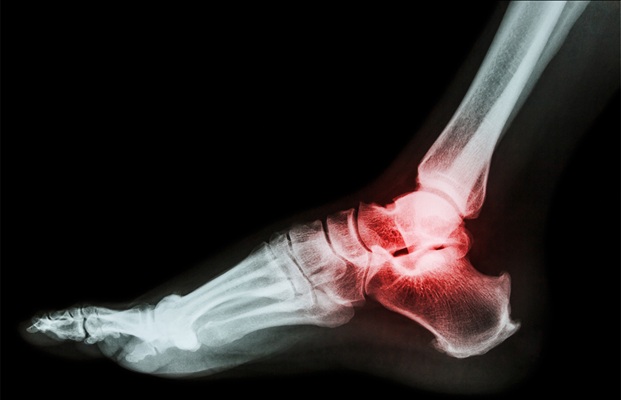

• USS Ankle (Ligament sprains, Achilles Tendon)